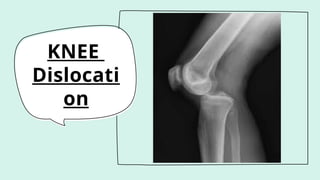

KNEE

Dislocati

on

• limb threatening- orthopaedic emergency

(POTENTIAL FOR VASCULAR DAMAGE)

•Result of high-energy injuries, such as

motor vehicle or industrial accidents.

•The dynamic and static stability of the knee

is conferred mainly by soft tissues

(ligaments, muscles, tendons, menisci) in

addition to the bony articulations.

•Significant soft tissue injury is necessary

for knee dislocation. (rupture of

cruciate,collateral, capsular elements &

menisci.